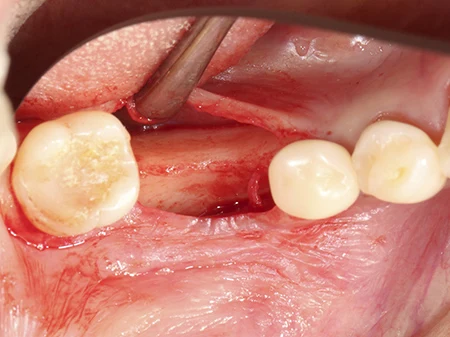

インプラントを埋入する前の状態。 奥歯が1本ない状態ですが、骨がやせてしまっており、人工骨で骨の移植と同時にインプラントを埋入していきます。

歯ぐきを切開し開いた状態。骨が前後の歯に比べて細いのがわかります。